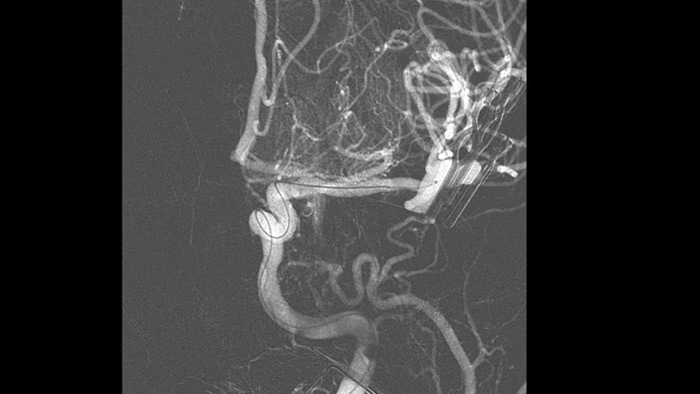

Dual Viewにより造影コーンビームCT撮影の早期相画像と後期相画像を並べて表示するデュアルビュー機能により、ペナンブラの識別や側副血行路の確認が可能です。

血栓に到達できるかどうか、およびどのルートを使用するかについて、十分な情報をに基づいて判断することができます。Roadmap Proは、放射線被ばくのバランスを保ちながら、重複する血管の視認性を向上させます。